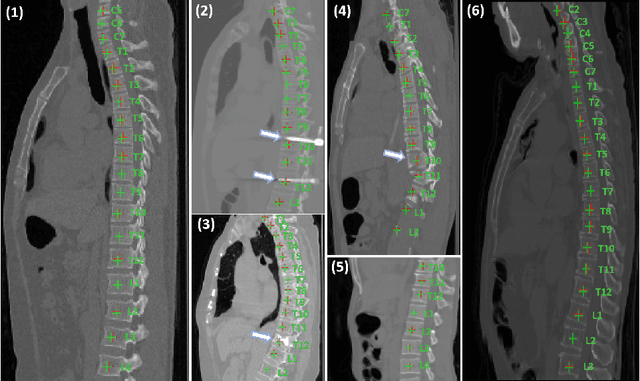

Abstract:Accurately localizing and identifying vertebrae from CT images is crucial for various clinical applications. However, most existing efforts are performed on 3D with cropping patch operation, suffering from the large computation costs and limited global information. In this paper, we propose a multi-view vertebra localization and identification from CT images, converting the 3D problem into a 2D localization and identification task on different views. Without the limitation of the 3D cropped patch, our method can learn the multi-view global information naturally. Moreover, to better capture the anatomical structure information from different view perspectives, a multi-view contrastive learning strategy is developed to pre-train the backbone. Additionally, we further propose a Sequence Loss to maintain the sequential structure embedded along the vertebrae. Evaluation results demonstrate that, with only two 2D networks, our method can localize and identify vertebrae in CT images accurately, and outperforms the state-of-the-art methods consistently. Our code is available at https://github.com/ShanghaiTech-IMPACT/Multi-View-Vertebra-Localization-and-Identification-from-CT-Images.